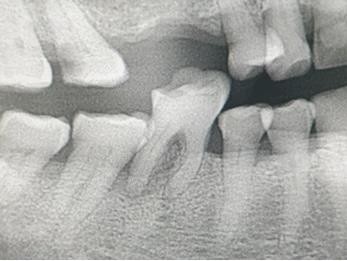

4. In the X ray bellow for which jaw periodontal bone loss is evident?